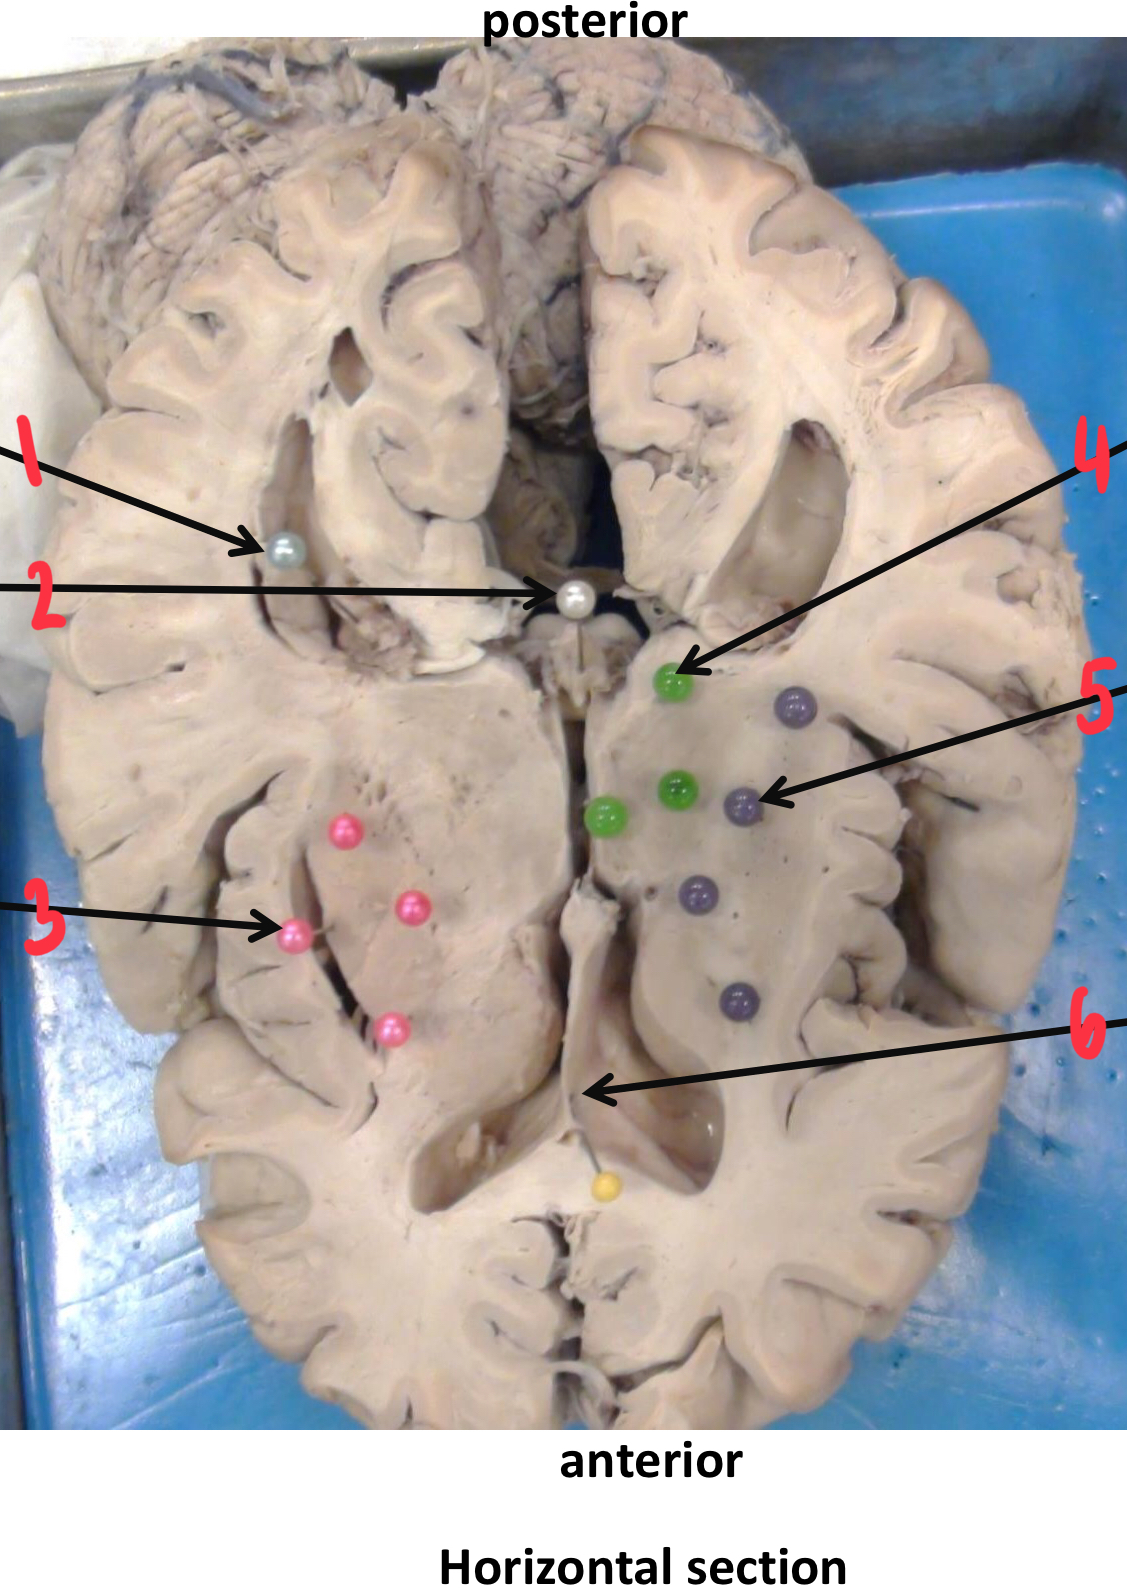

1

choroid plexus

2

pineal gland

3

lenticular (lentiform) nucleus

4

thalamus

5

internal capsule

6

septum pellucidum